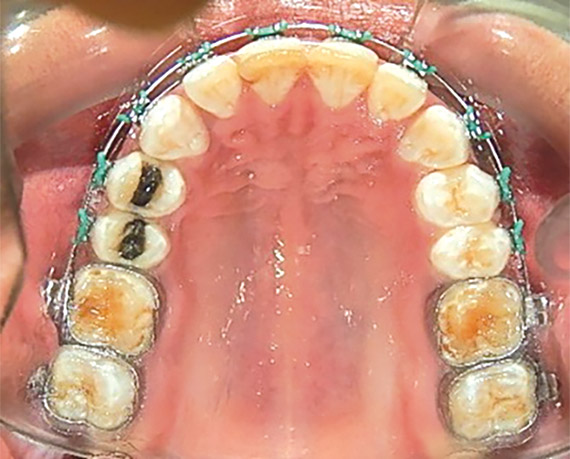

Se realizó una expansión dentoalveolar superior mediante un expansor con tornillo de 3 vías con efecto sagital y transversal, (Figura 9), preparación de la superficie dental para el bondeo de brackets por medio del arenado con partícula de sílice 60 μm a 40 lbs de presión con una angulación de 45° por un tiempo 3 a 4 segundos por diente, (Figura 10 y 11), y una fase ortodóncica con brackets prescripción Roth 0.022 x 0.028, tubos bondeables en 6's y 7's. Para la corrección del apiñamiento con alineación y nivelación utilizando una secuencia de arcos NiTi 0.014, 0.016 0.020 superior e inferior, NiTi 0.017 x 0.25 acero 0.018, 0.020 superior e inferior y stripping antero inferior. Para obtener la clase II molar y canina bilateral con mecánica de elásticos dobles bilaterales clase II largos con elásticos 1/8 6 ½ oz y stripping postero superior, para la corrección de la línea media con el uso de elásticos de línea media de 3/16 6 ½oz. La obtención del adecuado overjet y overbite se logró mediante el stripping, las cadenas intramaxilares y elásticos intermaxilares. Se obtuvo la máxima intercuspidación, paralelismo radicular y oclusión funcional en la fase de detallado mediante arcos de acero 0.017 x 0.025 y 0.019 x 0.025 superior e inferior, con dobleces de primer, segundo y tercer orden; restauración protésica en los dientes con fluorosis se trabajó mediante el tallado, la toma de impresiones, (Figura 10 y 11) y la colocación de la resina termocurada.

Figura 9. Aparato expansor.

Figura 10. Arenado de la superficie.

Figura 11. Arenado terminado.